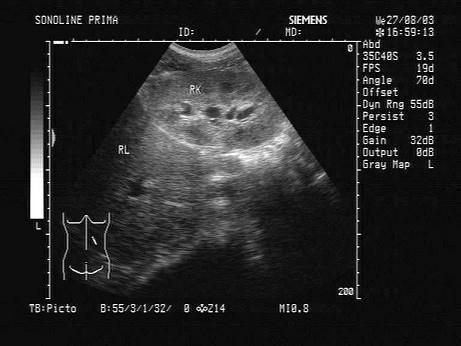

问题 某患者,既往有肾炎病史。因头晕,无尿三日入院,根据其肝右叶-右肾声像图,最可能的诊断为?(?)

选项 A.慢性肾衰 B.急性肾炎 C.肾结核 D.尿路结石 E.慢性肾炎

答案 E